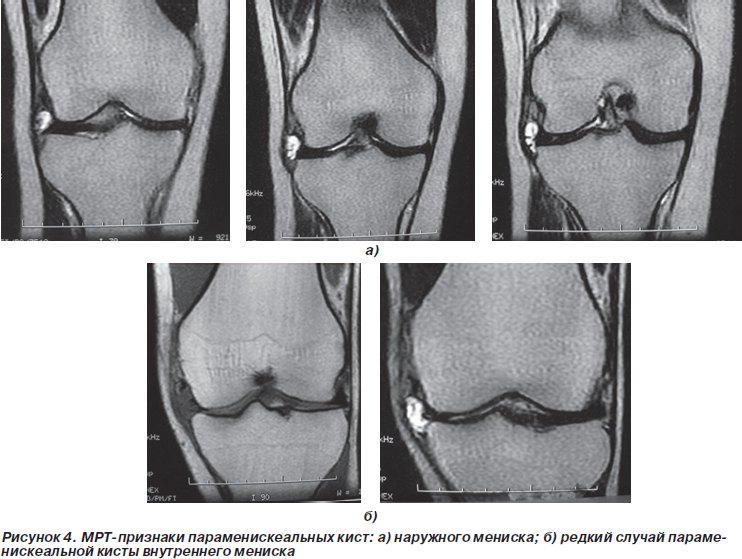

МРТ-признаки повреждения наружного мениска наблюдались у 3 пациентов, что было подтверждено при артроскопии. Однако еще у 2 пациентов при артроскопии был обнаружен продольный разрыв в области заднего рога наружного мениска, что ранее при МРТ отмечено не было. По всей вероятности, данное повреждение на срезе МРТ сливалось с зоной, в которой наружный мениск в норме не имеет связи с капсулой сустава.

Разрыв переднего рога наружного мениска был обнаружен по данным МРТ у 1 пациента, что не было подтверждено при артроскопии.

Неплохие результаты показала оценка данных МРТ при патологии менисков. Так, например, дегенеративные изменения менисков на начальных стадиях при артроскопии выявить, как правило, не удавалось, в то время как МРТ позволяла их определить.